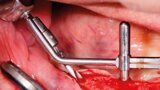

Protocollo SKY fast & fixed